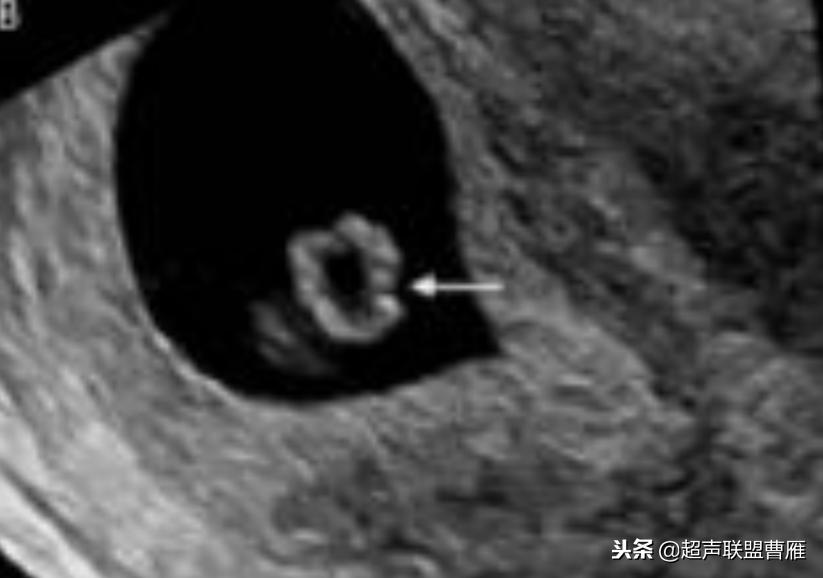

孕龄5.8周,胚极2.5mm,卵黄囊8mm,死胎

孕龄7+5周卵黄囊10.3mmx9.5mm,胚胎死亡

卵黄囊11*6.9mm 大卵黄囊

卵黄囊 羊膜囊 小胎儿雏形 (卵黄囊直径8.5mm)